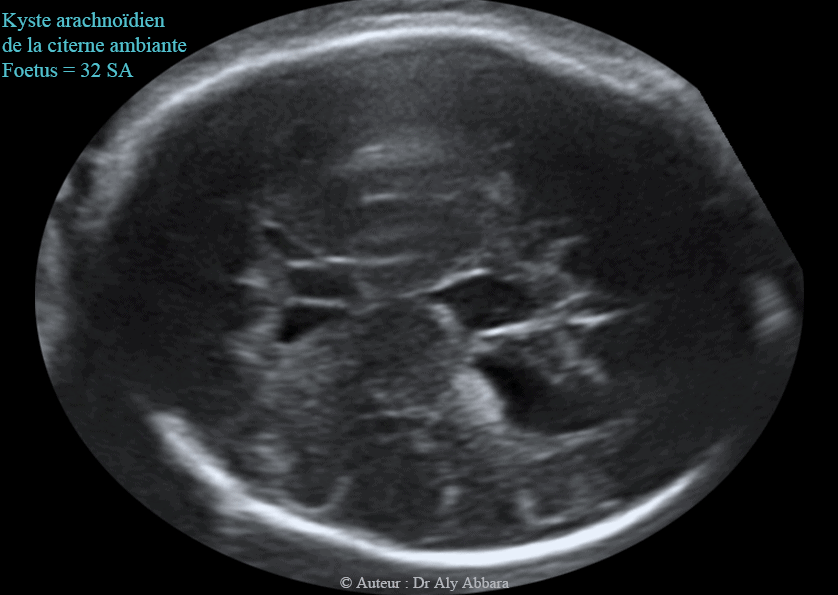

Echographie Kystes Arachnoidiens الكيسات العنكبوتية في الدماغ